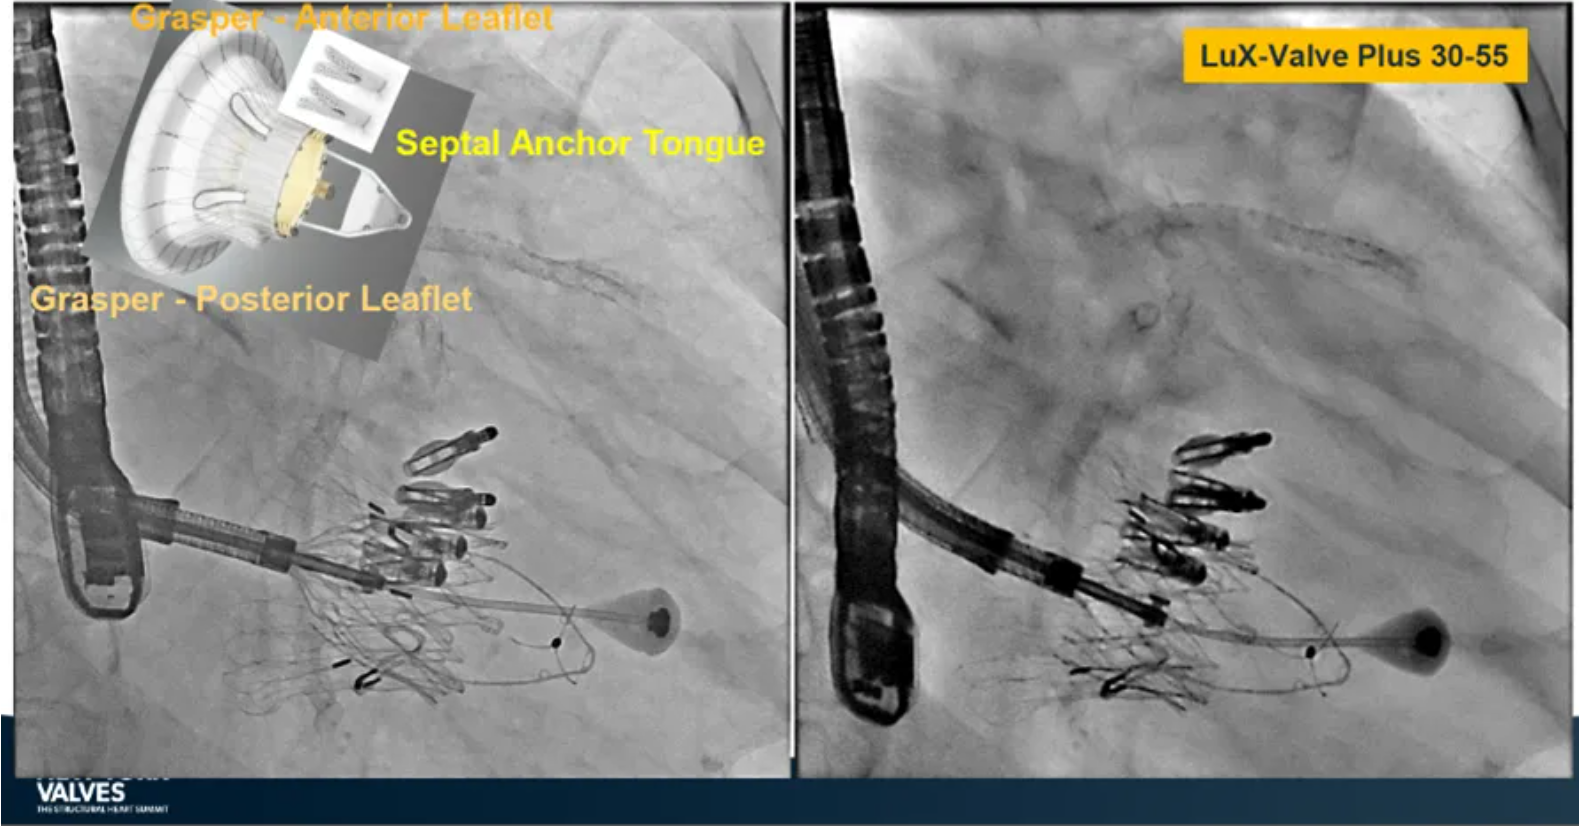

Granada教授表示,LuX-Valve Plus是一款不依賴于徑向支撐力固定的多功能TTVR器械,它的創新設計(室間隔錨定和瓣葉夾持件)提供了多樣的固定和穩定技術。多中心臨床試驗研究TRAVEL II 展現了LuX-Valve Plus的安全性和有效性,能實現較短的器械操作時間,較低的復合事件發生率,并在6個月期時顯著降低三尖瓣反流等級,以及帶來心功能和生活質量等指標上的明顯改善。

蘇澤宇教授介紹到,受限于三尖瓣特殊的解剖結構及后期病理性改變,并非所有的解剖都適用于T-TEER療法及外科手術進行治療,因此TTVR器械的選擇成為了新的臨床需求,并帶來完全消除反流等級的可能性。LuX-Valve Plus即是這樣一款經頸靜脈入路的三尖瓣置換系統,能覆蓋較廣范圍的瓣環尺寸,并帶來較低的起搏器植入率。

來自中國上海復旦大學附屬中山醫院的魏來教授在2024年臺北瓣膜高峰論壇上分享了他使用LuX-Valve Plus治療三尖瓣反流的經驗。魏來教授闡述道,隨著療法演變,目前全球市場有以LuX-Valve Plus及其他產品為代表的經導管三尖瓣介入置換系統,逐漸成為重度三尖瓣反流的一線治療方案。他介紹到,LuX-Valve Plus創新的室間隔錨定和經頸靜脈入路的方式,能夠帶來安全穩定的錨定效果及較短的輸送行程;其可調彎的輸送系統能保證同軸性,從而快速和安全地將人工瓣膜送達目標手術區域,有效降低入路周邊解剖組織并發癥及術中出血風險。